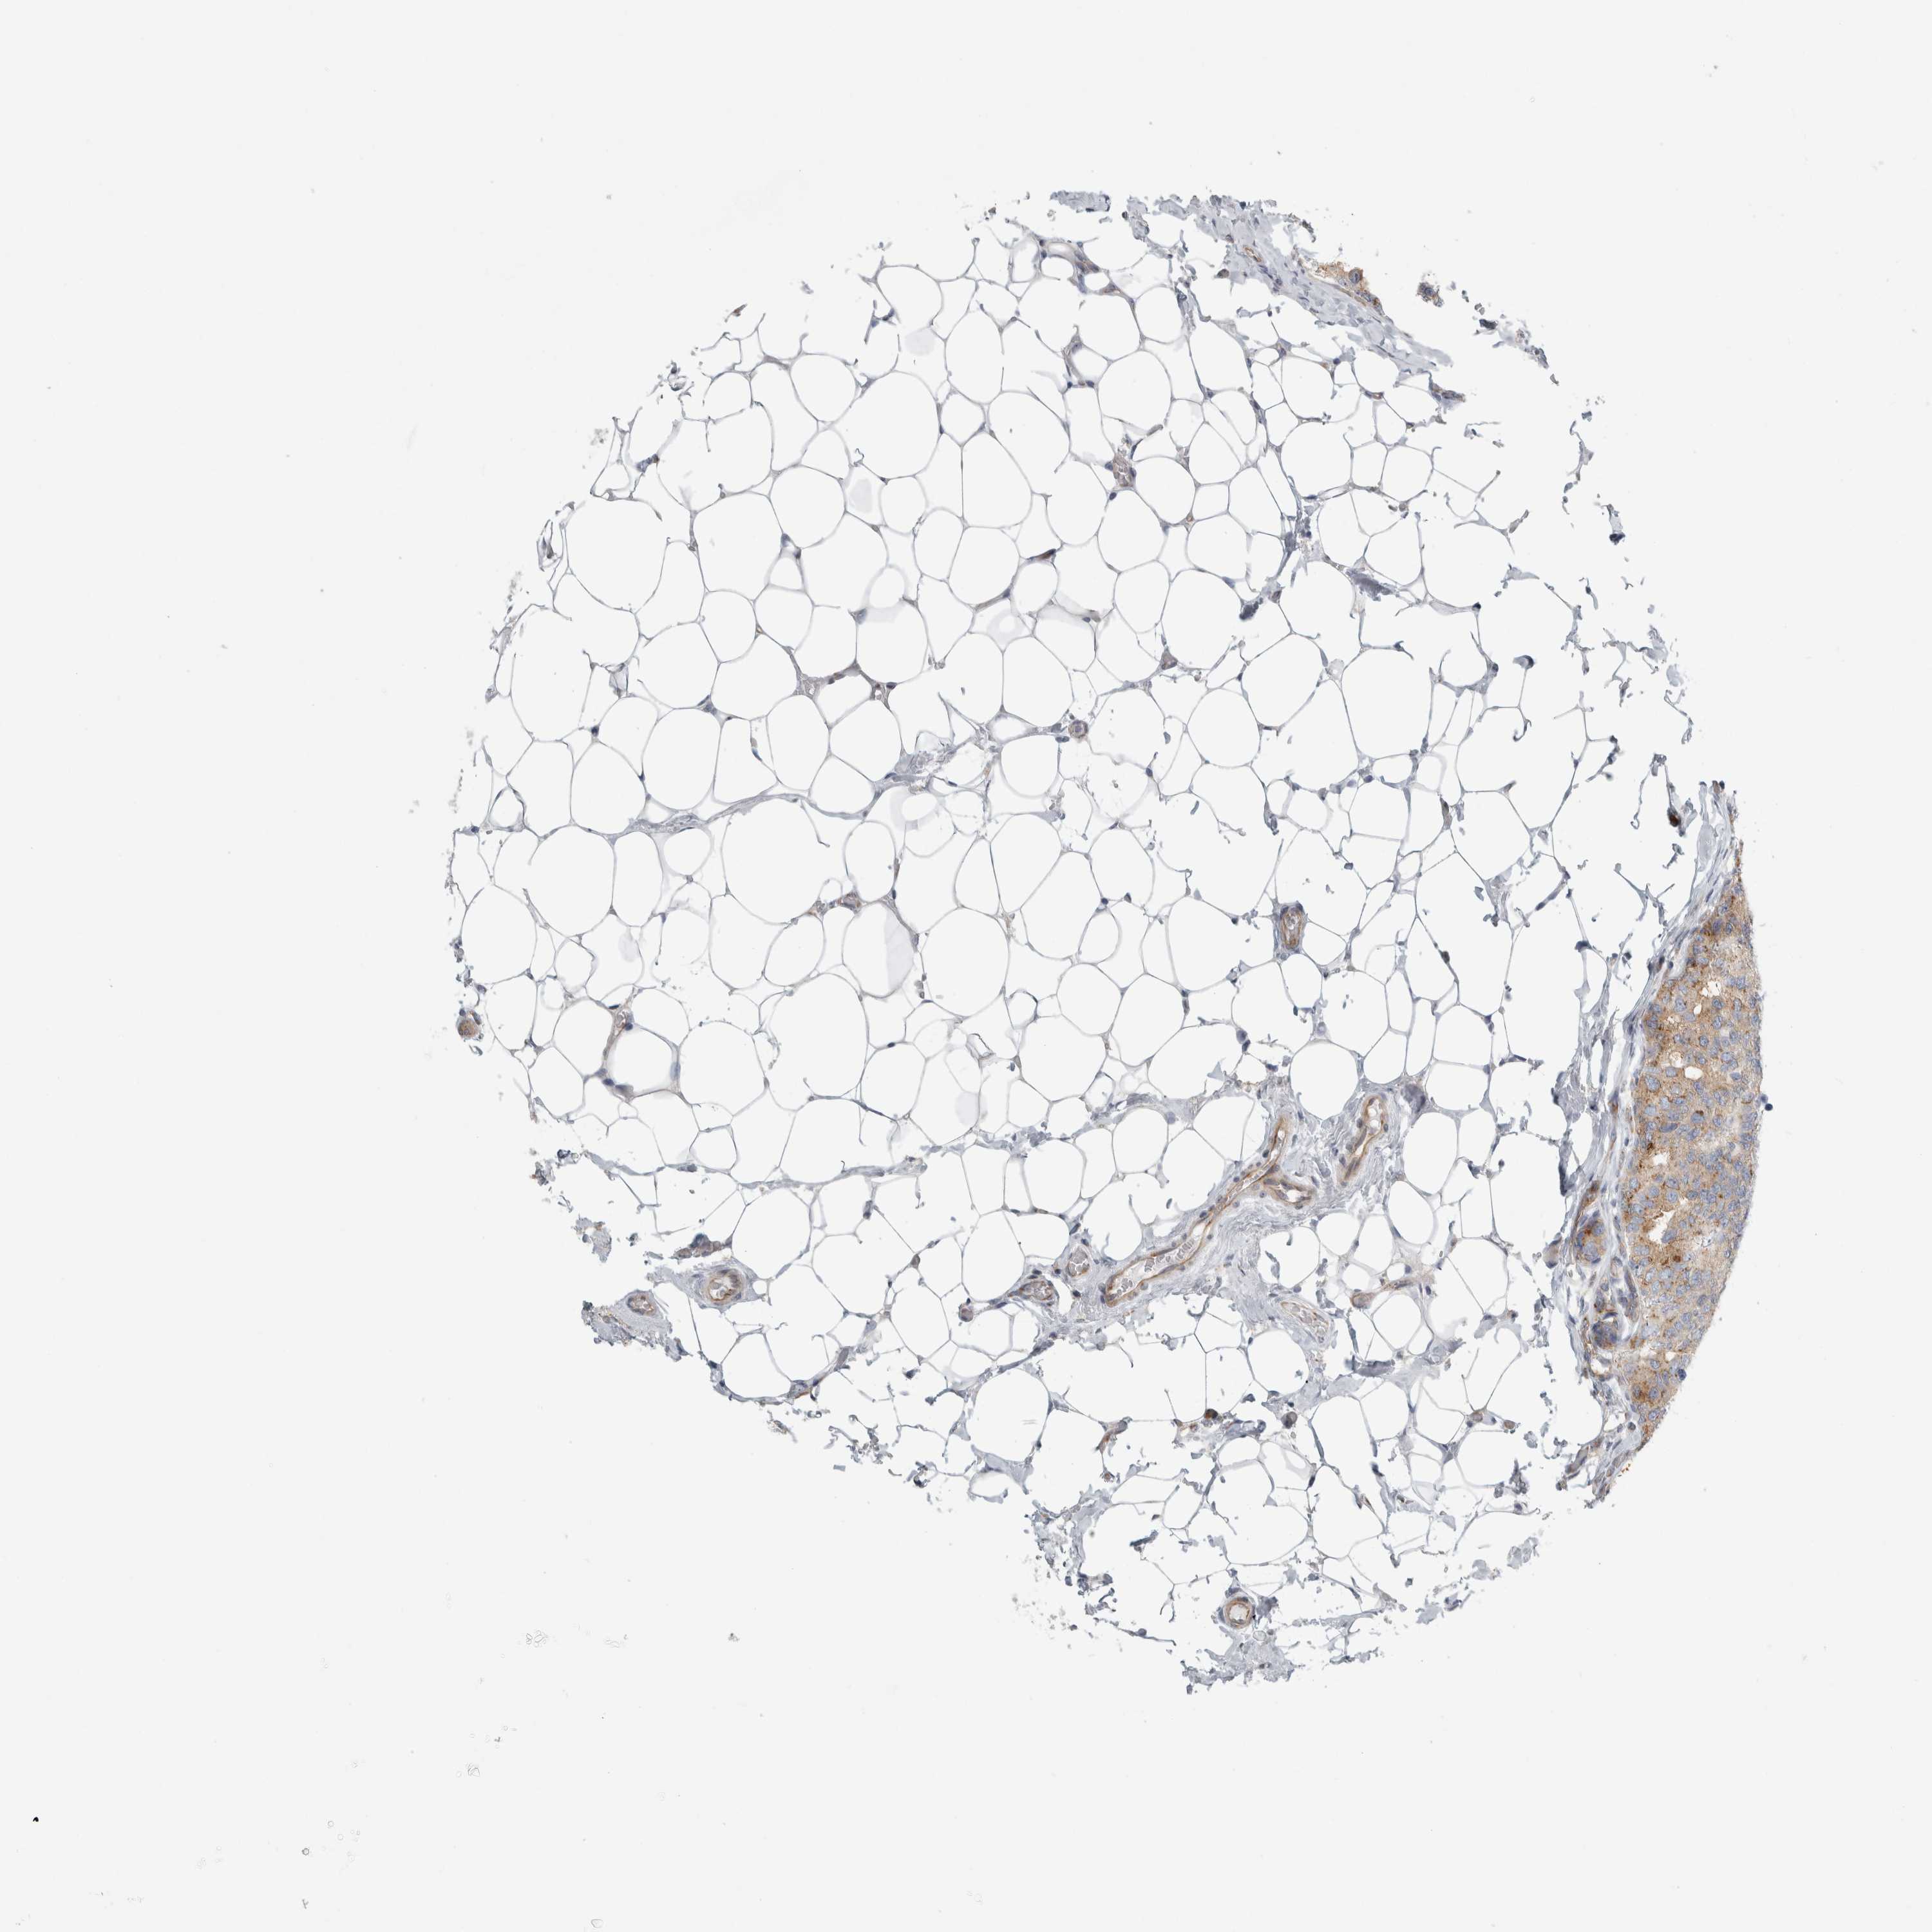

BRCA TCGA BRCA VALIDATION PROTEIN EXPRESSION